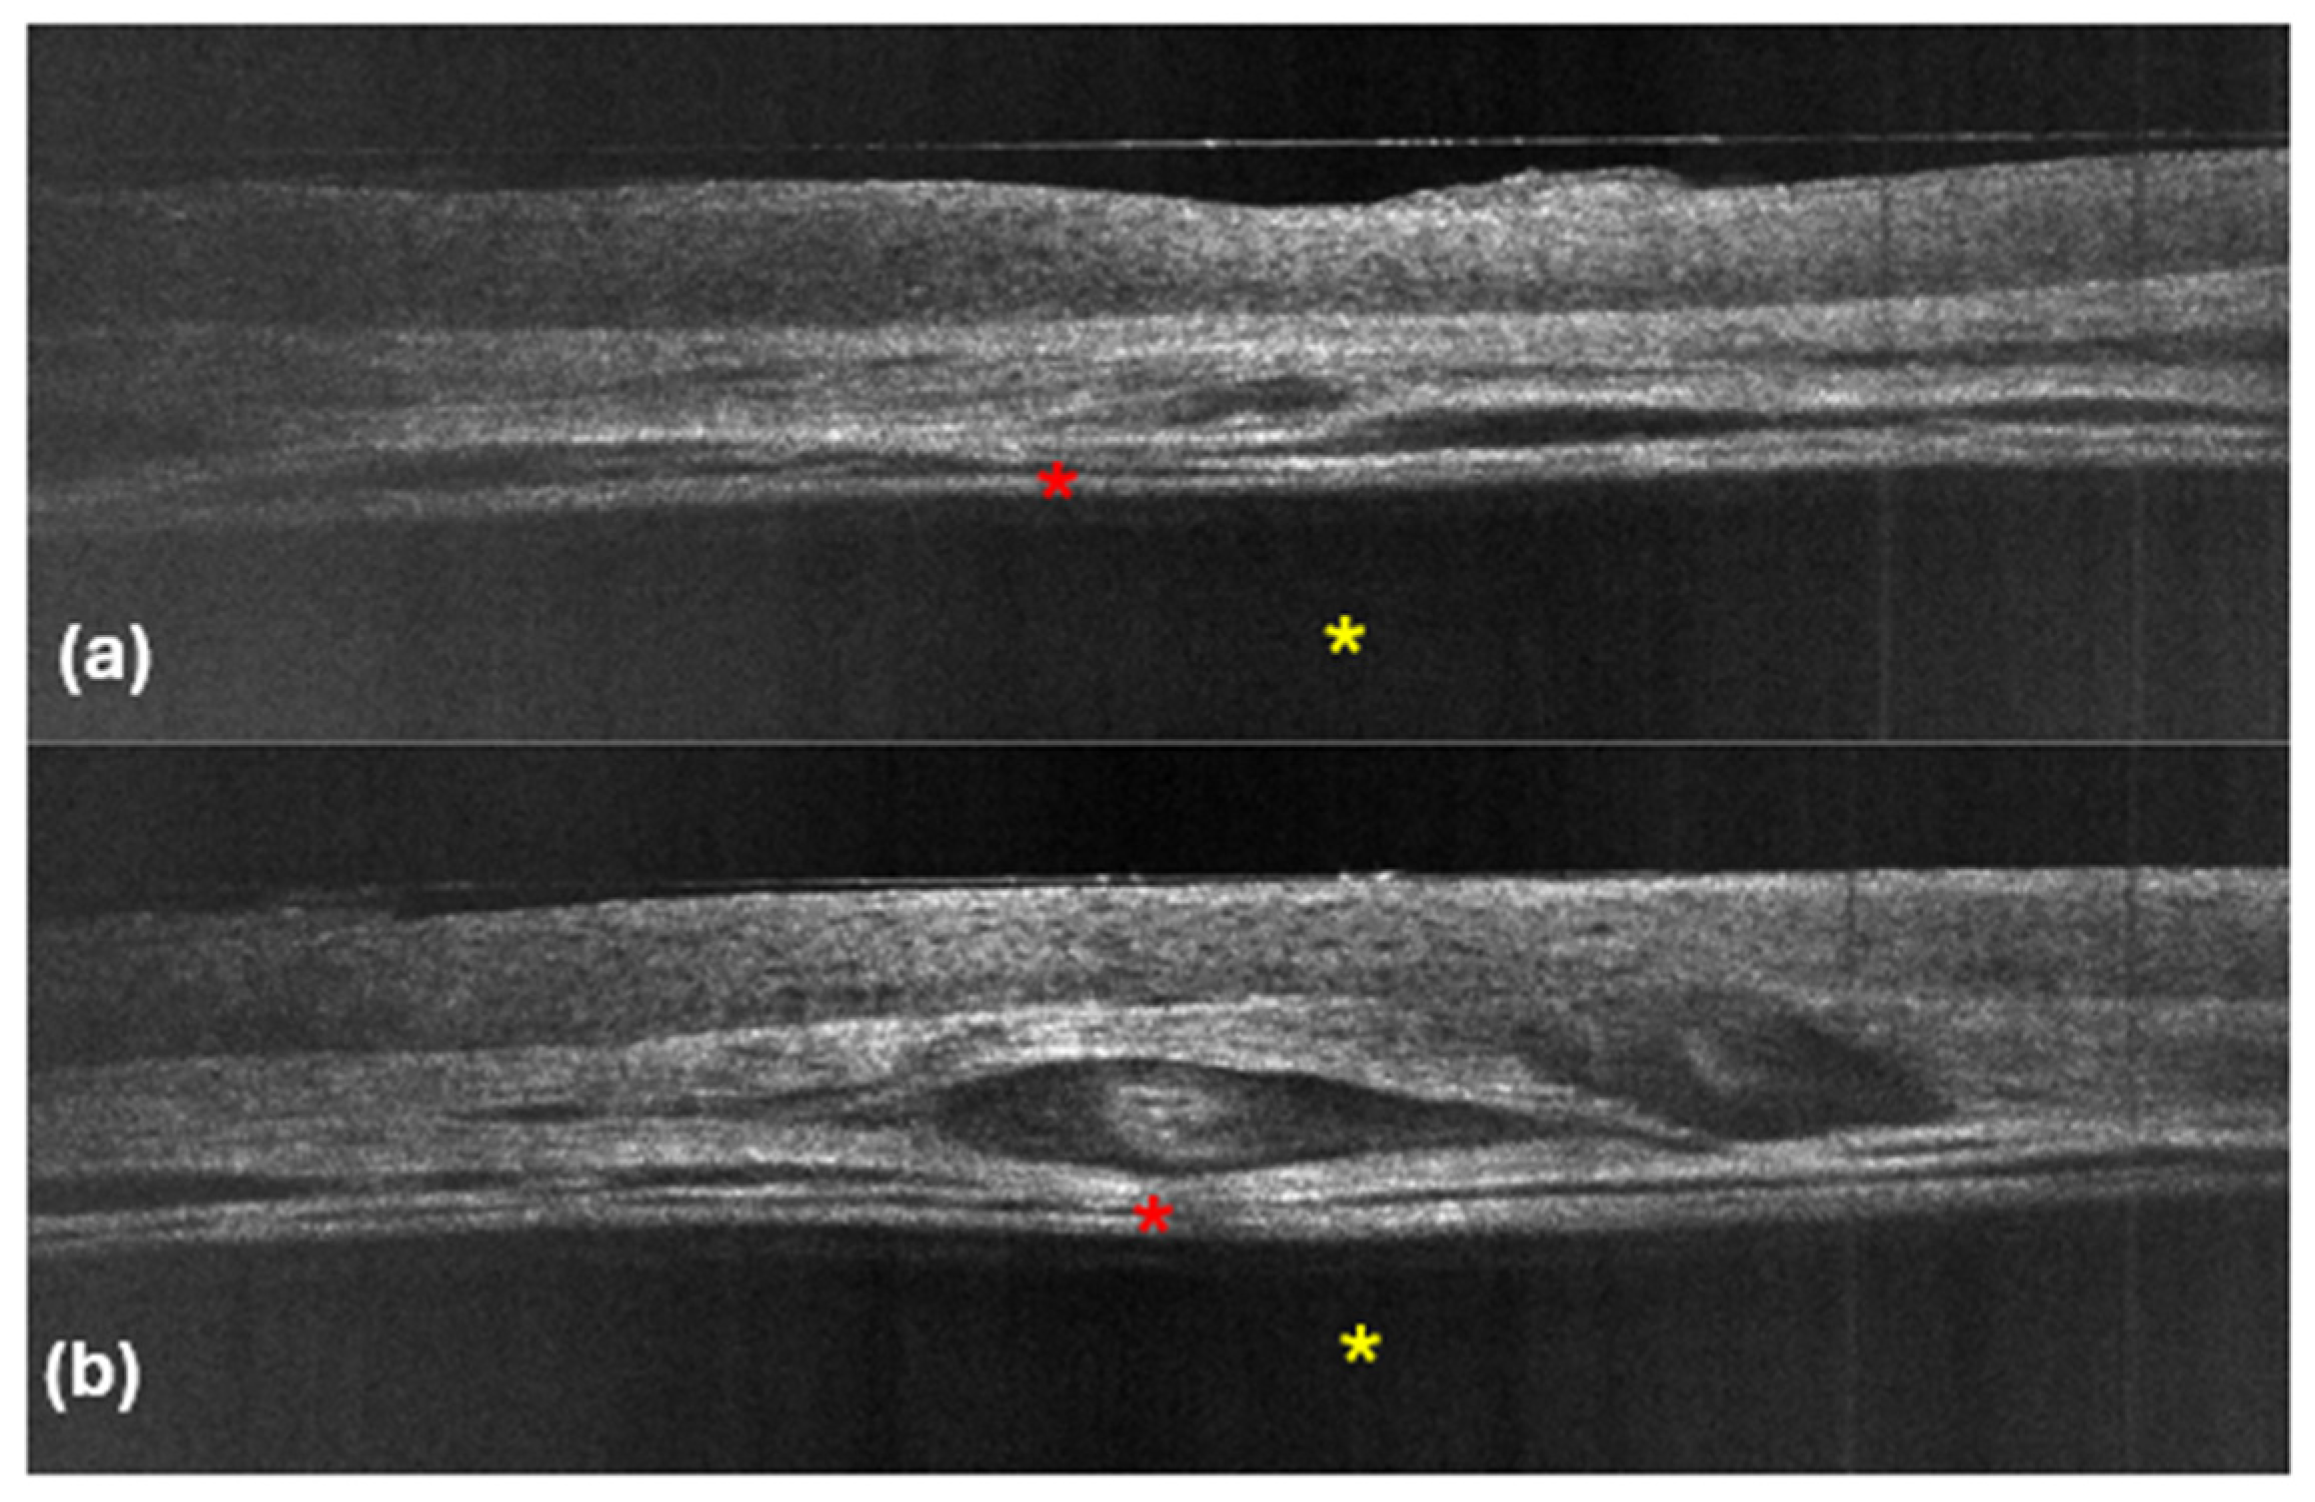

To the best of our knowledge, Verzì et al. [11] were the first to describe the LC-OCT features of five hidrocystomas, which showed a normal epidermis and a dermal cupoliform hyporeflective structure with a thick, hyperreflective border surrounding the dark content. In our study, all five lesions exhibited a similar hyporeflective cupoliform area, which was well defined by a bright and thick upper contour, corresponding to the top of the hidrocystoma (Figure 2).

Regarding the content of the dermal structure, 80% of the lesions were filled with a completely homogeneous hyporeflective material, indicating a liquid nature, which is consistent with the fluid content typically found in hidrocystomas. Interestingly, one lesion exhibited a slight hyperreflective substance within a darker region, suggesting that this material may contain elements such as lipofuscin or other debris that can contribute to the varying echogenicity observed in these tumors [20]. The hyporeflectivity is likely indicative of liquid, while hyperreflectivity can suggest the presence of denser substances.

In terms of vascular structures, they were not consistently visible across all cases. Some LC-OCT images revealed dilated vessels situated above the cupoliform area, which may reflect the vascular supply typical of these lesions. A thick hyperreflective contour surrounded the cupoliform structure, and in certain instances, a cleft was observed between this contour and the adjacent dermis, possibly indicating a delineation between the cystic lesion and surrounding tissues. Notably, we did not detect any architectural abnormalities or the presence of small bright cells in the epidermis overlying the hidrocystoma, which is a crucial finding.

Basal cell carcinoma typically presents with distinct architectural abnormalities, branched lobules with a millefeuille pattern, clefting, and a darker rim. These characteristics are essential for the diagnosis of BCC and were absent in our hidrocystoma cases, reinforcing the benign nature of these lesions. Additionally, the lack of such features emphasizes the importance of LC-OCT in identifying the unique characteristics of hidrocystomas, thereby aiding in their differentiation from BCC. Thus, by employing LC-OCT alongside other diagnostic modalities, clinicians can achieve a more accurate diagnosis, ensuring that appropriate management strategies are implemented for both benign and malignant skin lesions. Our LC-OCT findings align with well-established histopathological characteristics of hidrocystomas, which are cystic spaces in the dermis typically lined by a dual-layered epithelium [21,30] (Figure 3).

Indeed, within the thick hyperreflective contour visible in LC-OCT, it was often possible to identify two bright layers of cells (Figure 4).

However, the deeper margin of the cystic lacunae was not visible in any image because it was situated too deep.

Figure 2. LC-OCT images (a,b). Vertical sections showing hyporeflective cupoliform area, well defined by a bright and thick upper contour (red asterisks), filled with a completely hyporeflective material (yellow asterisks).